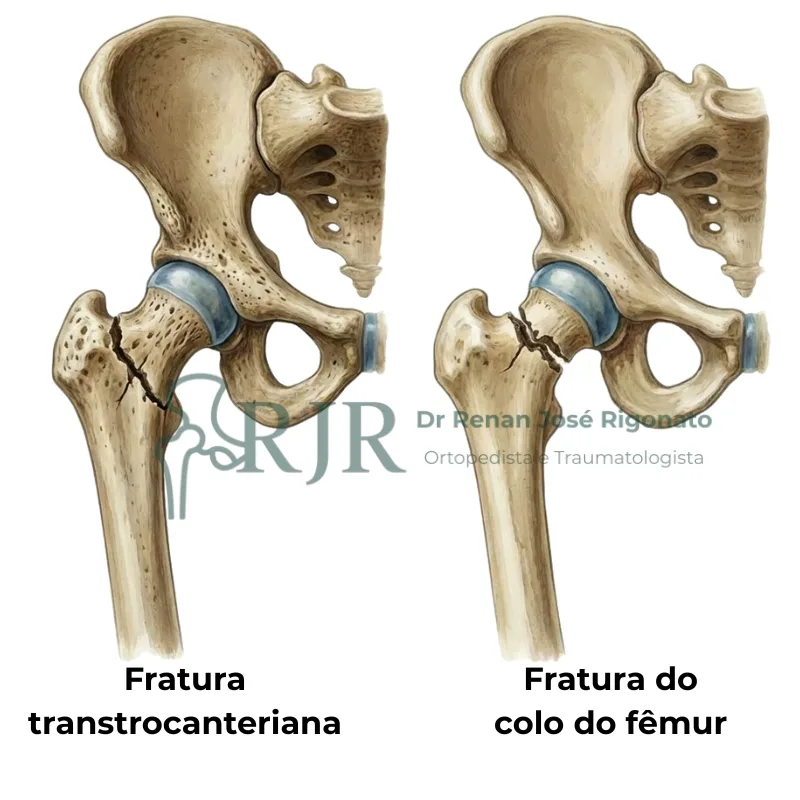

Fraturas do fêmur

As fraturas do fêmur proximal acontecem principalmente no colo do fêmur e região transtrocanteriana. Ambas exigem tratamento imediato.